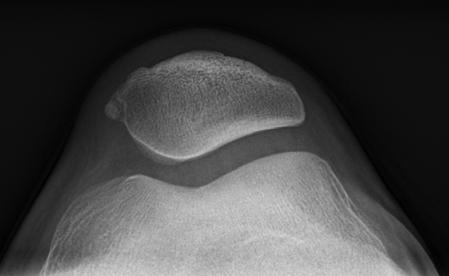

sá sem er mikilvægastur fyrir stöðugleika hnéskeljarinnar. Hnéskelin snertir trissuna fyrst við 20 til 30° beygju um hnéð og við frekari beygju helst hnéskelin stöðug vegna lögunar trissunnar (mynd 1)

Mynd 1

Hliðlægt

Miðlægt